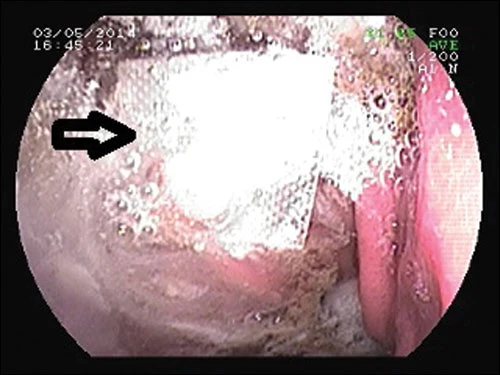

Vỉ thuốc được gắp ra ngoài thành công